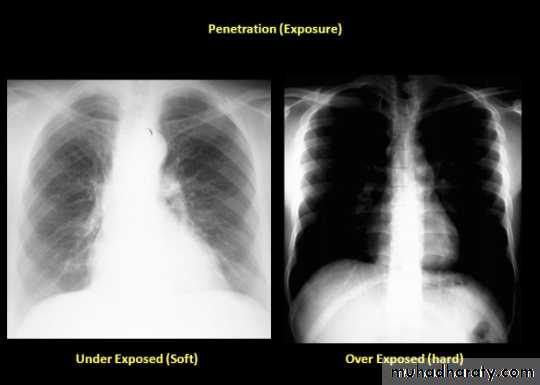

8- assess technical quality of the film: correctly exposed routine PA CXR is one in which the ribs and spine behind the heart can be identified but lung not overexposed.straight film is one where the medial ends of clavicles are equidistant from thoracic verteb.

Good penetration